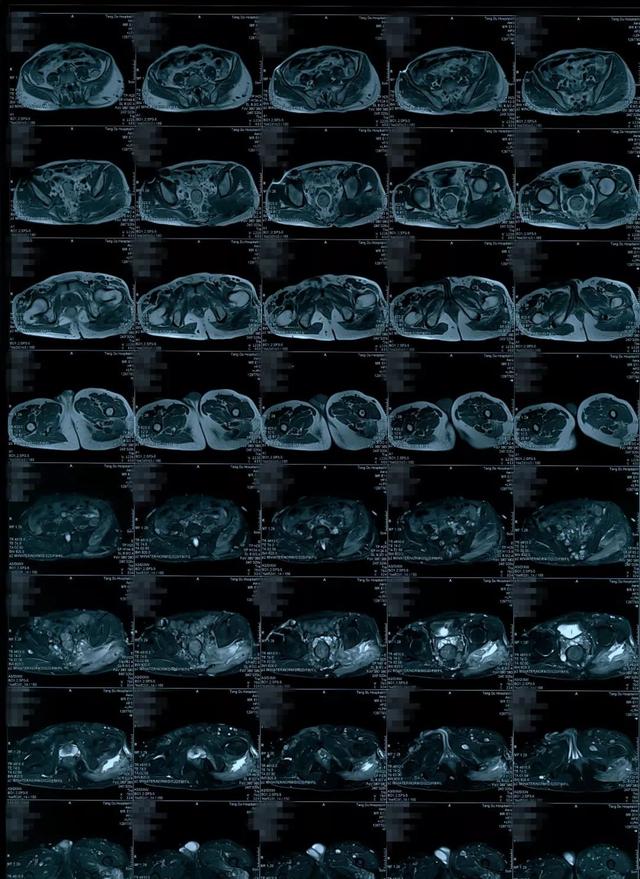

肠系膜丨纤维瘤病

图片尺寸1080x607